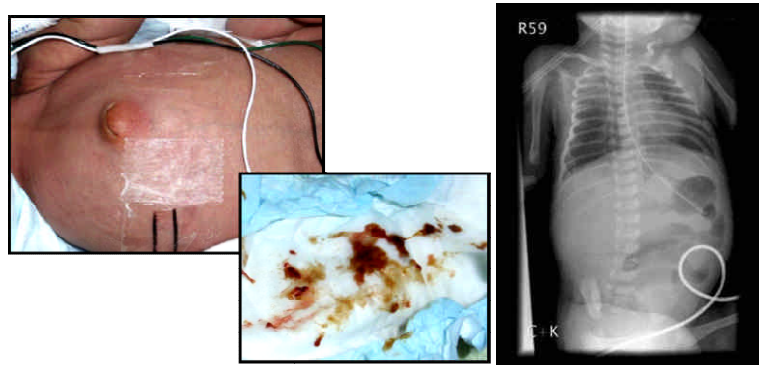

2 一個 7 天大男童,因為腹脹及黃疸求診。 出生體重為 2,550 公克,出生週數。身體診察顯示倦怠、活力不佳,肝臟可摸到兩指幅。血液檢查白血球 8,280μL,其中 segment占15%,band form 占22%,lymphocyte 占 30%,monocyte占1%,eosinophil占1.2% 。血紅素15 g/dL,血小板 220,000/μL。ALT 77 U/L、AST 72 U/L腹部X 光、腹部皮膚及糞便如下,臨床診斷最可能為下列何者 (A)intestinal obstruction (B)acute gastroenteritis (C)milk allergy(D)congenital megacolon

76 懷孕週數 22 週出生的早產兒,出生後一星期突發腹脹、食慾不振、活力變差,仰躺腹部 X 光片如圖, 則最常見原因為何? (A)腸胃炎(gastroenteritis) (B)膽道閉鎖(biliary atresia) (C)巨腸症(megacolon) (D)腹腔積氣(pneumoperitoneum)